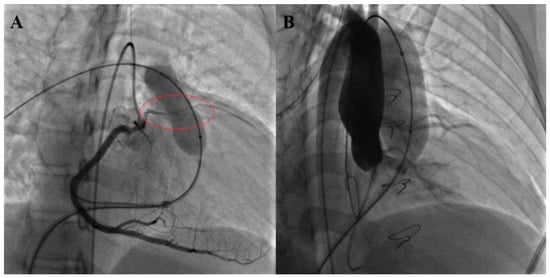

- Garay, F.; Pan, X.; Zhang, Y.J.; Wang, C.; Springmuller, D. Early experience with the Venus P-Valve for percutaneous pulmonary valve implantation in native outflow tract. Neth. Heart J. 2017, 25, 76–81. [Google Scholar] [CrossRef] [PubMed]

- Morgan, G.; Prachasilchai, P.; Promphan, W.; Rosenthal, E.; Sivakumar, K.; Kappanayil, M.; Sakidjan, I.; Walsh, K.P.; Kenny, D.; Thomson, J.; et al. Medium-term results of percutaneous pulmonary valve implantation using the Venus P-Valve: International experience. EuroIntervention 2019, 14, 1363–1370. [Google Scholar] [CrossRef] [PubMed]

- Jin, Q.; Long, Y.; Zhang, G.; Pan, X.; Chen, M.; Feng, Y.; Liu, J.; Yu, S.; Pan, W.; Zhou, D.; et al. Five-year follow-up after percutaneous pulmonary valve implantation using the Venus P-Valve system for patients with pulmonary regurgitation and an enlarged native right ventricular outflow tract. Catheter. Cardiovasc. Interv. 2024, 103, 359–366. [Google Scholar] [CrossRef]